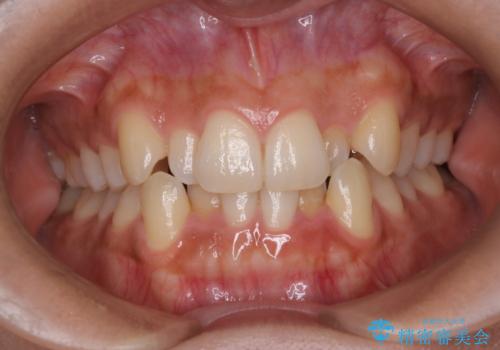

【重度叢生ワイヤー矯正】きれいな歯並びにしたい

- きれいな歯並びにしたいとの希望を持って来院された患者様です。

上下左右小臼歯を抜歯する治療計画を立て審美装置にて治療を行いました。

骨格的3級傾向もあり、咬合関係を仕上げるのに時間がかかりましたが、患者様には大変満足していただけました。

難しいケースでしたが、矯正用アンカースクリューを用いながら、臼歯関係もきれいに仕上げることができました。